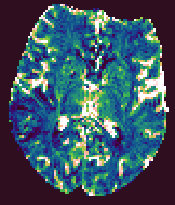

Brain Perfusion Output Parametric Images

The Brain Perfusion analysis produces five output images, that

have the same base name, but have the output parameter name

appended. These are:

- CBF. Cerebral blood flow, with units of mls blood / 100g tissue / minute.

- CBV. Cerebral blood volume, with units that indicate the blood

volume as a percentage of the total tissue volume.

- MTT. The mean transit time, in seconds.

- TTP. The time from contrast arrival to the peak in capillary concentration, in seconds.

- RMSE. A measure of the goodness of fit. This root-mean-square of the residuals between the

fitted curve and the time-series data.

These output images are in floating-point format, and can be

viewed using Jim. The output images will be of the same

image type as the first input image.

Example output images from the Brain Perfusion Tool.

|

| Cerebral Blood Flow |

Cerebral Blood Volume |

Mean Transit Time |

Time-to-Peak |